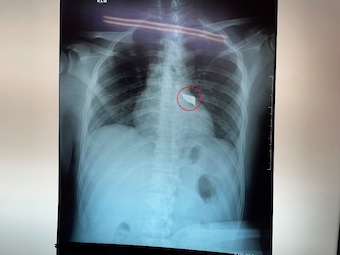

Nam thanh niên 30 tuổi bị dao đâm vào cột sống. Khiến phải mang cả mũi dao cắm sâu vào lưng đến bệnh viện cấp cứu. Các bác sĩ đã phải nhanh chóng lấy mũi dao ra khỏi người bệnh nhân.

Chiều 8/4, tin từ bệnh viện Đa khoa Trung ương Cần Thơ, các bác sĩ khoa Ngoại Thần kinh đã phẫu thuật cấp cứu lấy thành công mũi dao đâm vào cột sống nam bệnh nhân T.H.T.H, 30 tuổi, ngụ tỉnh Sóc Trăng.

Theo lời người thân bệnh nhân, H. bị đâm bằng dao sau lưng trái và nhanh chóng được đưa vào bệnh viện địa phương xử trí cấp cứu ban đầu. Sau đó, H. được chuyển đến bệnh viện Đa khoa Trung ương Cần Thơ lúc 10h40 ngày 7/4.

Tình trạng lúc nhập viện, bệnh nhân H. tỉnh, niêm hồng, than đau lưng, khó thở nhẹ với vết thương lưng thành ngực sau cạnh trái cột sống đoạn ngực 4-5 rỉ máu, còn dị vật, không tê yếu chi, dấu hiệu sinh tồn ổn định.

Các bác sĩ khoa Cấp cứu nhanh chóng xử trí cấp cứu và thực hiện các xét nghiệm, siêu âm, chụp Xquang tim phổi thẳng, chụp cắt lớp vi tính lồng ngực… Việc hội chẩn phẫu thuật được ê-kíp bác sĩ khẩn tiến hành và thống nhất phương án xử lý thám sát vết thương và lấy dị vật cấp cứu.

Sau 90 phút phẫu thuật, ê-kíp phẫu thuật gồm: Bs.CK2 Trần Văn Minh – Phó Trưởng, khoa Ngoại Thần kinh, Bs. Nguyễn Châu Thanh, Bs.CK1 Nguyễn Văn Vĩnh – Khoa Phẫu thuật – Gây mê hồi sức đã lấy thành công mũi dao dài 5x2cm ra ngoài.

Theo Bs.CK2 Trần Văn Minh, may mắn là trường hợp này mũi dao chưa gây vết thương tủy sống, nếu tổn thương tủy sống bệnh nhân sẽ có rối loạn cảm giác, rối loạn vận động, liệt tủy không hoàn toàn với các biến chứng dò dịch não tủy, nhiễm trùng, áp xe, viêm màng não tủy.

Nếu mũi dao đi sâu hơn nữa sẽ chạm gây thương tổn các tạng xung quanh, tùy theo vị trí tổn thương: Động mạch tủy sống, phổi màng phổi, động mạch chủ, động mạch cảnh, gan thận, ruột…

Bác sĩ khuyến cáo, với những trường hợp tương tự điều đặc biệt lưu ý là không được tùy tiện rút vật xuyên thấu ra khỏi vết thương tại hiện trường tai nạn hoặc ngay cả trong phòng cấp cứu, mà cần được đánh giá bằng các công cụ chẩn đoán hình ảnh như siêu âm, xquang, chụp cắt lớp vi tính trước để có thể lường được mức độ tổn thương và các nguy cơ tai biến có thể xảy ra khi rút vật xuyên thấu.